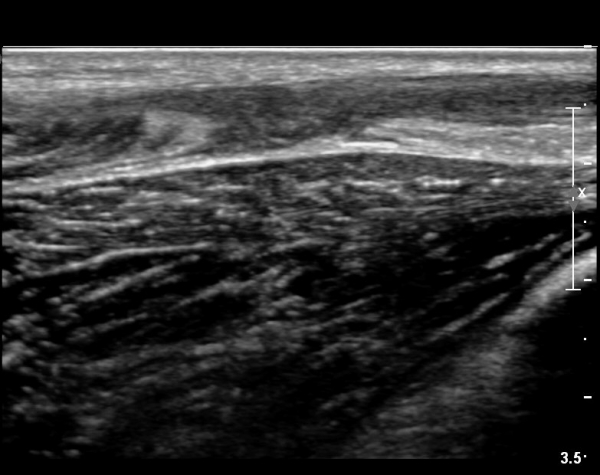

[¹ß¸ñ] simultaneosus tear of GCM and achiles tendon

abrupt leg pain developed during foot volleyball

he walk with severe limping with no weight bearing on rt. leg. on examination, there is local tendernes at GCM and achiles tendon, severe pain with ankle dorsiflexion.

ÃÊÀ½ÆÄ °Ë»ç